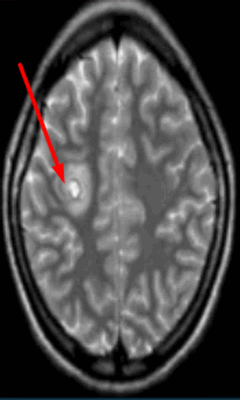

Обычно очаги демиелинизации выглядят как множественные мелкие участки гиперинтенсивного МР-сигнала, расположенные в одном или нескольких отделах головного мозга. По степени их распространенности, давности и одновременности возникновения врач судит о масштабах развития заболевания.

Очаг демиелинизации на МРТ